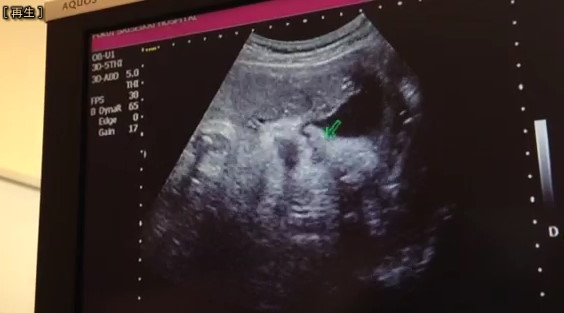

なんか鼻べちゃな気がするんだけど、気のせいか?

鼻が一番親子似る部分だと思うんだけど、、、、

べちゃってないか、狭いからなだけか?

やっぱベチャってる